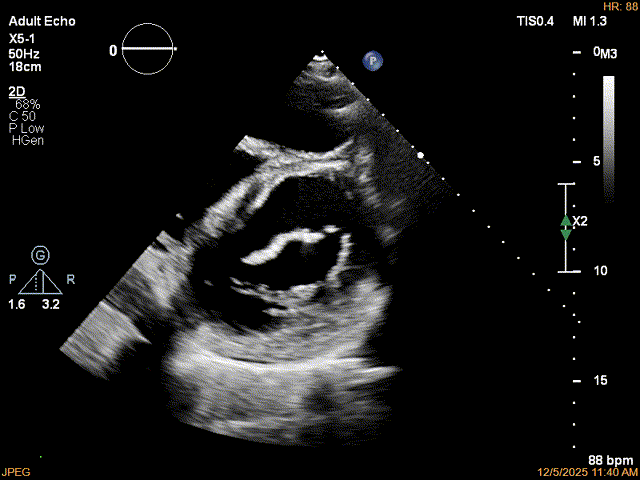

为了避免长时间TEE对食道造成损伤,术前即刻3D-TEE短时进一步明确二尖瓣病变相关解剖情况。

3D-TEE二尖瓣相关解剖学参数:后叶长度:22-25mm,前叶长度:31-34mm;瓣环AP径:47mm,ML径:48mm;瓣口面积:约7.8cm²;脱垂宽度:30mm,最大连枷间距:14mm。

术前即刻TEE进一步明确了二尖瓣反流的机制(DMR)及反流程度(5+),重点完善了病变区域二尖瓣解剖结构的评估,预估手术难点/影响手术效果的解剖结构为冗长的二尖瓣后叶(PML约25mm),宽大的脱垂(Flail Width约30mm),超大的连枷间距(Flail gap约14mm)。